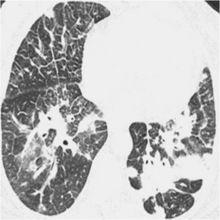

隱源性機化性肺炎2.2 CT的特點 :90%的COP患者CT表現為氣腔實變。將近50%的病例CT顯示病變沿胸膜下或支氣管周圍分布,以下肺區更明顯。當出現實變就能見到支氣管氣像。實變區常見輕度柱狀支氣管擴張。將近50%的病例常出現沿支氣管血管分布的小結節影。大約60%的病例出現磨玻璃影,通常與肺實質相伴隨。胸腔積液罕見,大多數COP患者經治療後影像學改善。然而未經治療時,一個部位的肺實質異常可能消散或擴大,甚至出現在新的部位。

2.3 影像學鑑別診斷: 呈現實變影的COP患者影像學鑑別診斷包括肺泡癌、淋巴瘤、血管炎、結節病和感染(尤其是結核或不典型的分枝桿菌感染)。但實變影位於胸膜下時,應考慮慢性嗜酸性粒細胞肺炎的診斷。表現為多發塊影的患者需要與肺部轉移瘤、淋巴瘤和肺部感染,如細菌性栓塞鑑別,多數情況下經支氣管肺活檢有助於排除上述疾病,具備相應的臨床表現。經抗生素治療數周,實變影仍然增長,CT顯示以支氣管周圍或胸膜下分布為主的實變影,高度提示COP。